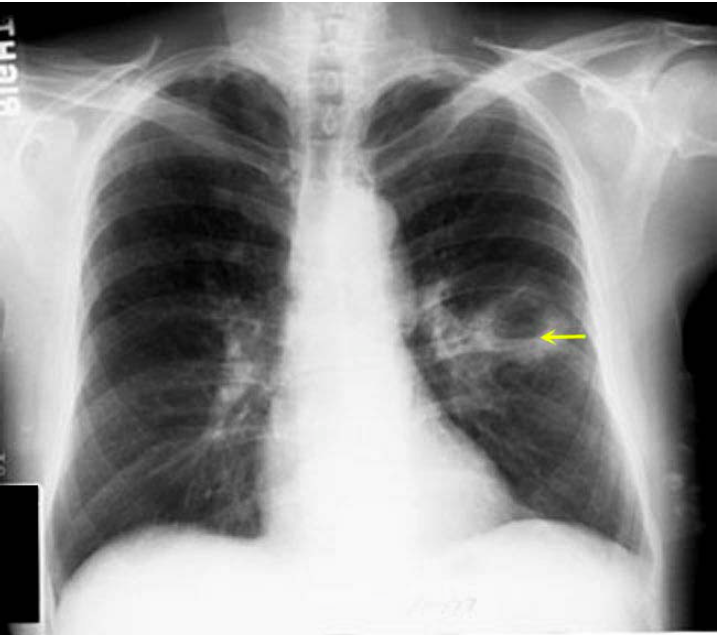

What is shown in the image?

Aspiration Lung Abscess

Why does aspiration lung abscess occur in the superior segment of lower lobes?

These areas are gravity dependent when lying down